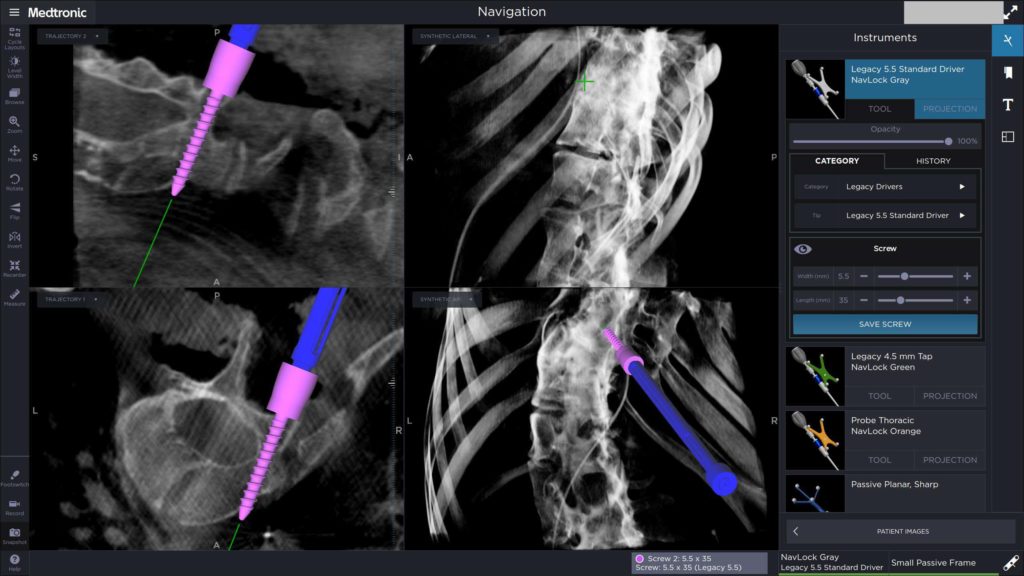

- α

- β

Εικόνα 7 (α,β)

Μετεγχειρητική Μετωπιαία και πλαγία ακτινογραφία της χειρουργηθείσης περιοχής του σκολιωτικού κυρτώματος. Οι διαυχενικοί κοχλίες έχουν τοποθετηθεί εκατέρωθεν του επιπέδου της οστεοτομίας.

Ο ασθενής κινητοποιήθηκε άμεσα την επομένη της επέμβασης και βάδισε ομαλά, εξήλθε δε μετά 4ήμερο χωρίς να φορά κηδεμόνα. Η μετεγχειρητική πορεία ήταν εντός των φυσιολογικών πλαισίων και μετά 30ήμερο άρχισε να έχει ήπιες δραστηριότητες.

Ο τελευταίος κλινικο-ακτινολογικός έλεγχος έγινε 10 μήνες μετά την επέμβαση ο οποίος έδειξε την καλή θέση των υλικών σπονδυλοδεσίας. Ο ασθενής επανήλθε σε πολύ ήπιες δραστηριότητες – όχι χειρωνακτικές- δόθηκαν οδηγίες για προοδευτική αύξηση των δραστηριοτήτων το επόμενο εξάμηνο όπου και θα επανεξετασθεί η γενικότερη κατάστασή του.